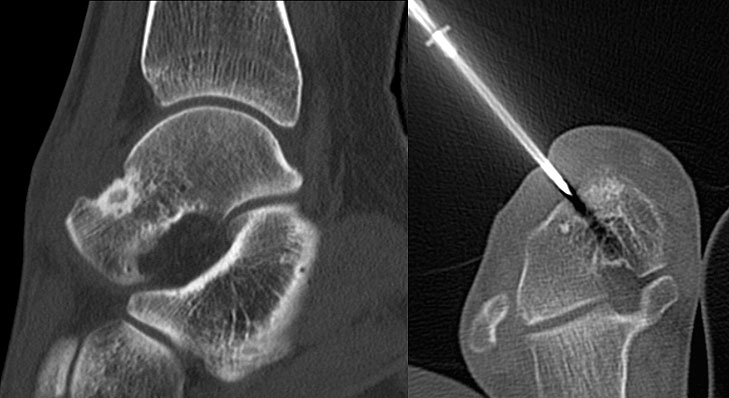

Die Computertomographie (CT) wird seltener als die MRT herangezogen um eine spezi­fischen Artdiagnose zu finden, liefert aber wertvolle Informationen zur Kortikalis­beschaffen­heit (Kontinuität, Stärke, enostale Arrosion) unterschiedlichster Knochenläsionen. Insbe­sondere die enostale Kortikalisarrosion, wie sie häufig bei chondrogenen Tumoren anzu­treffen ist, kann konkrete Hinweise liefern, die in Zusammenschau mit histologischen Befunden zu einer definitiven Diagnose führen (siehe Spezifische Entitäten: Enchondrom vs. atypischer chondrogener Tumor/Chondrosarkom). Die Computertomographie ist außerdem hilfreich in der Abgrenzung komplexer anatomischer Strukturen (z.B. 3D-Rekonstruktion) und sehr kleiner Knochenläsionen. Bei der Diagnose des Osteoidosteoms bleibt die CT Mittel der Wahl um die charakteristischen Veränderungen in der bildgebenden Diagnostik exakt darzustellen (Abb. 6). Die Gewebedichte von weichteiligen Tumoren, insbesondere von intra- und extraossären Lipomen, kann im Vergleich zum subkutanen Fettgewebe mithilfe der Houndsfield-Skala beurteilt werden.

Axiale CT-Aufnahmen eines Osteoidosteoms im Bereich des Calcaneus mit typischer Nidusbildung und perifokaler Sklerose (links). Bildgesteuerte Thermofrequenzablation der Läsion (rechts).